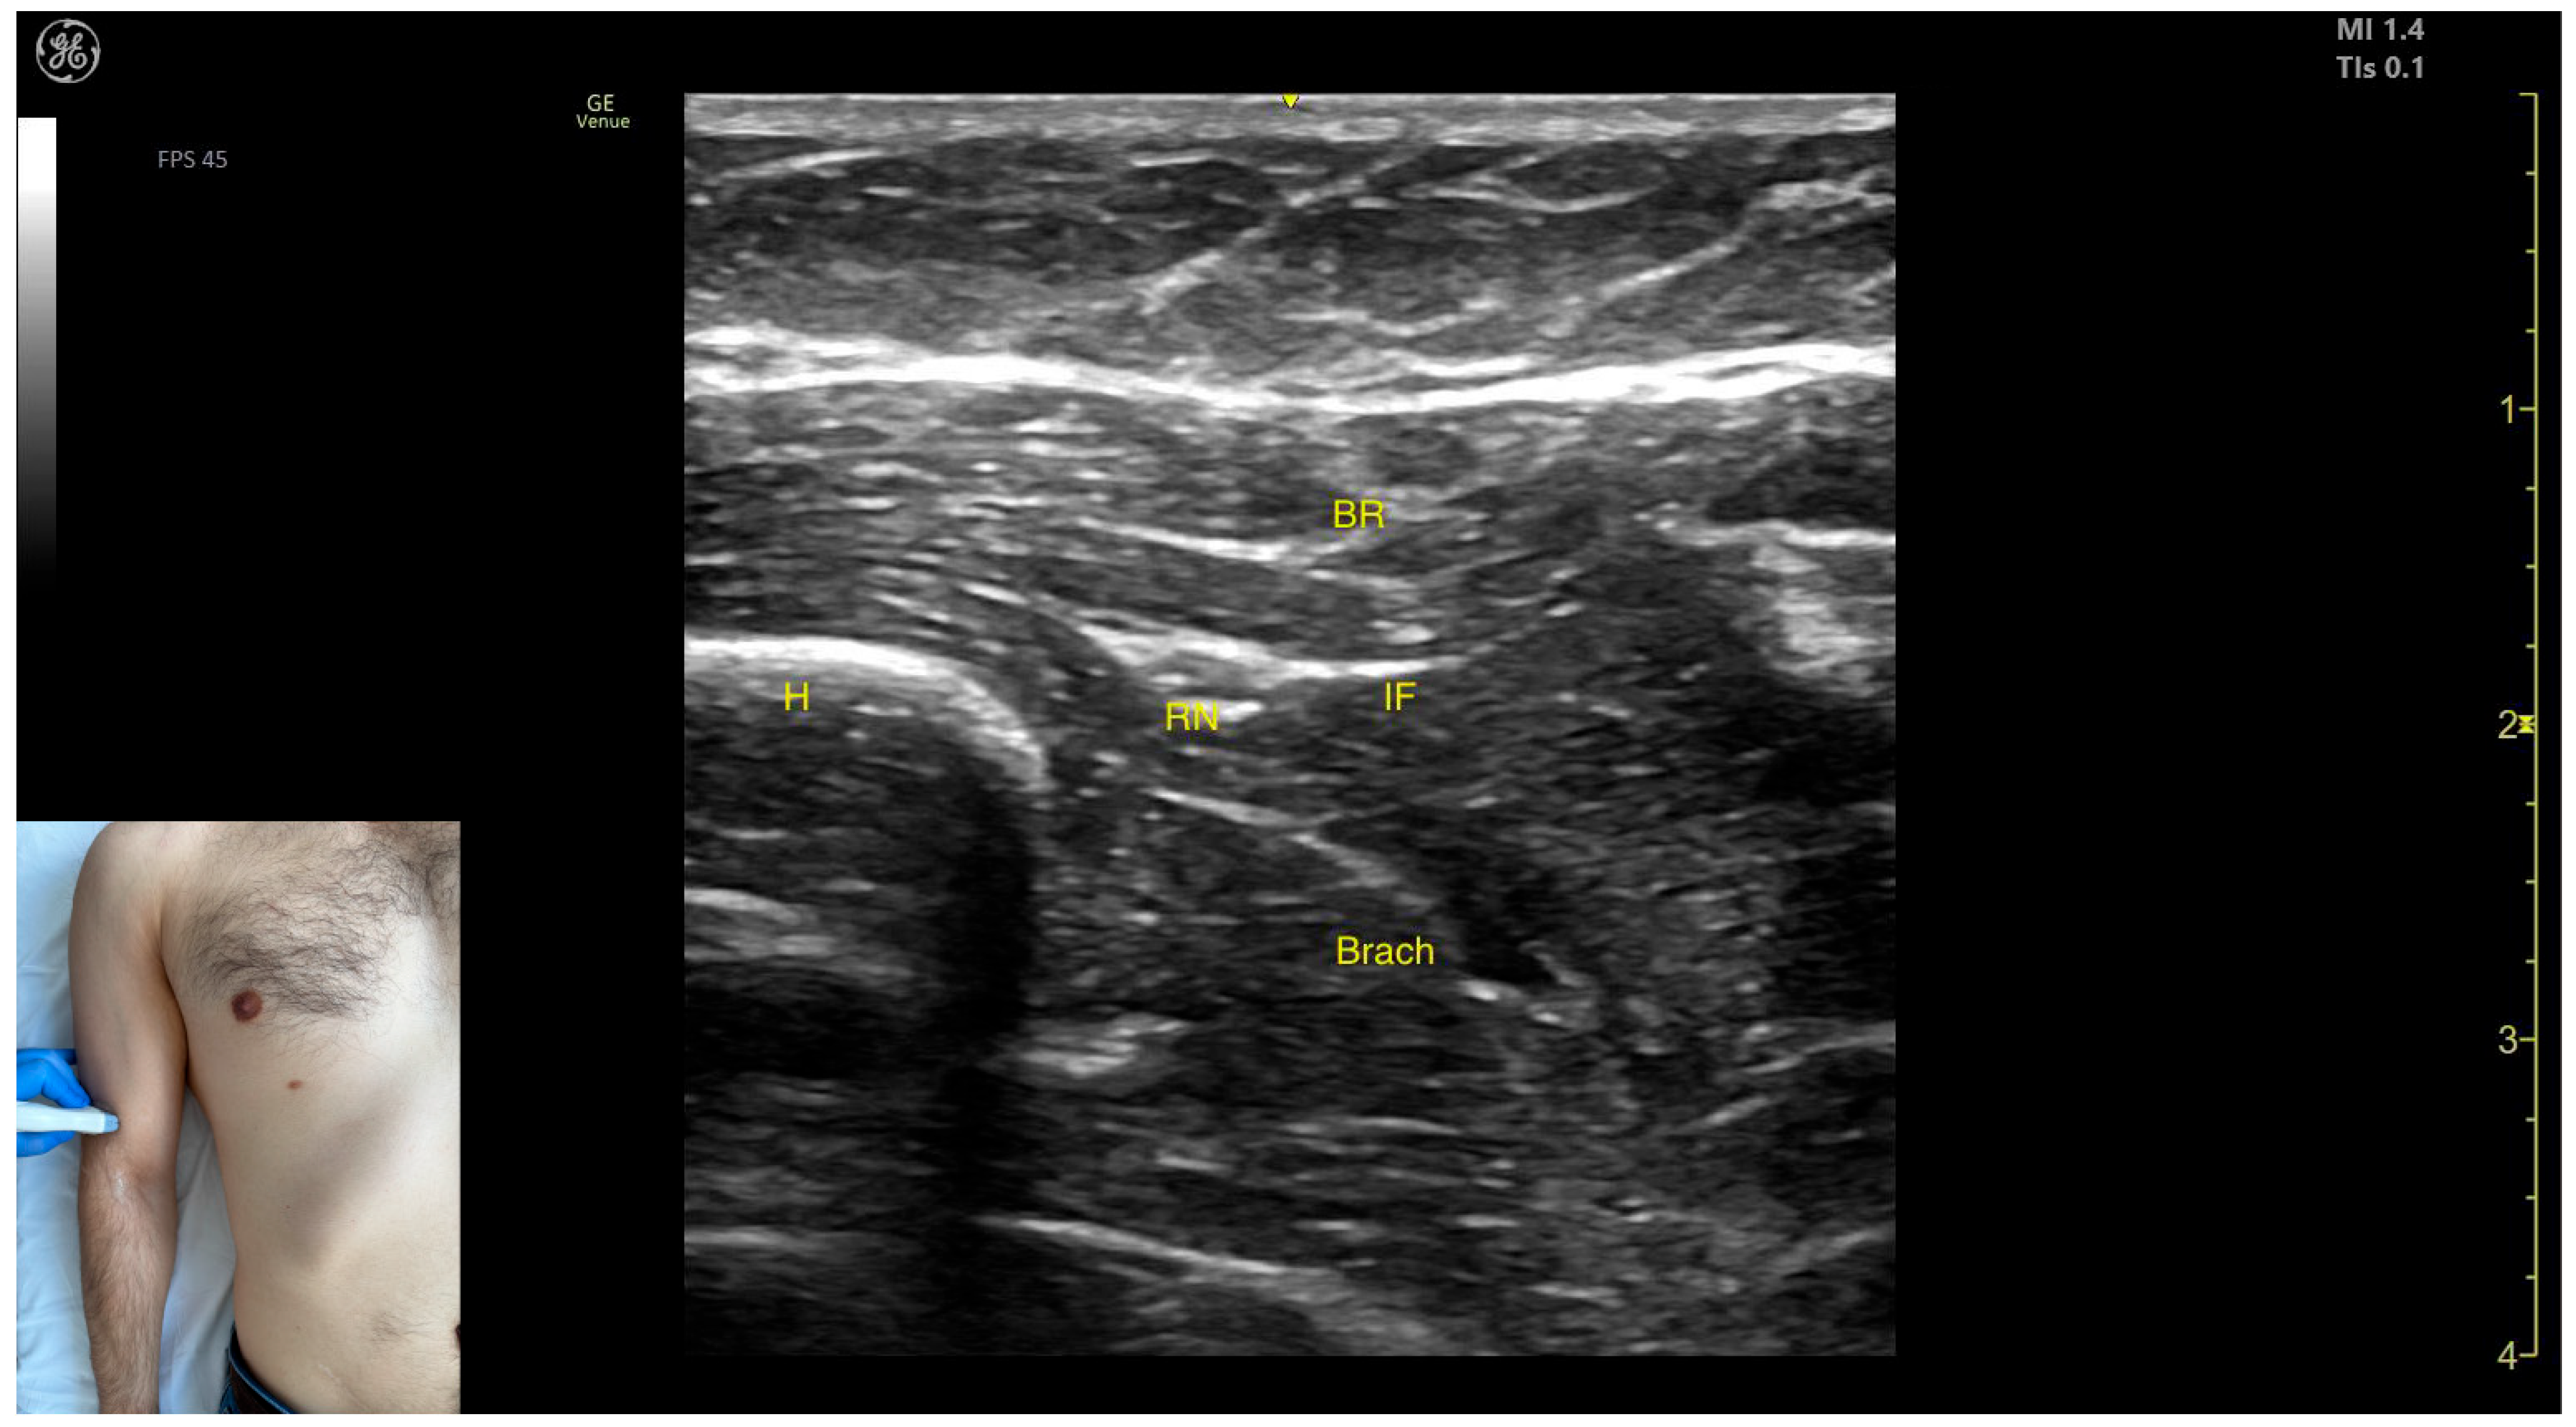

- Muscle position: It represents the first muscle mass located superficial to the cortical bone of the humerus on the anterior lateral surface of the arm.

- Innervation: The radial nerve is seen superficially in the intermuscular fascia, which separates the Brach from the brachioradialis muscle.

- External fascia: The Brach has a pronounced fascia that separates it from the brachioradialis. A very thin fascia separates it from the BB during BoNT-A injections.

- Dynamic evaluation: During dynamic evaluation, proximal scanning toward the shoulder joint shows the radial nerve moving closer to the cortical bone of the humerus before following an oblique path and disappearing from the view as it enters the posterior compartment of the arm. Medial scanning reveals the BB muscle superficial to the Brach. Muscle contraction of the Brach is visible during forearm flexion at the elbow joint, as it is the only pure flexor of the elbow [7].

- Muscle position: It represents the most superficial muscle mass on the anterolateral surface of the arm at this level.

- Innervation: The radial nerve is located deep within the muscle, enclosed in the intermuscular fascia that separates the BR from the Brach muscle.

- External fascia: The BR has a pronounced fascia that separates it from both the Brach and the subcutaneous plane during BoNT-A injections.

- Dynamic evaluation: During dynamic evaluation, distal scanning toward the lateral epicondyle reveals the division of the radial nerve into its superficial branch and deep branch (posterior interosseous nerve), with the deep branch continuing along the anterolateral proximal third of the forearm.